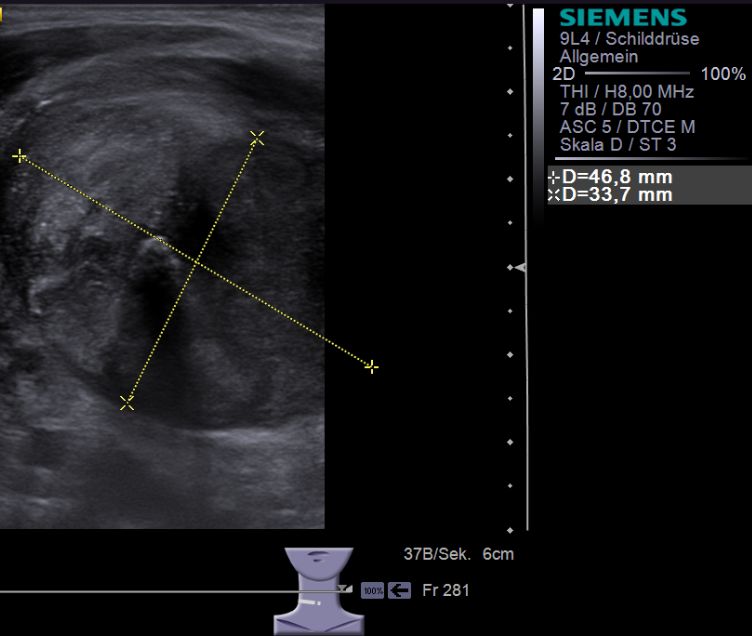

44-jähriger Mann mit verhorntem

Plattenepithelkarzinom der Schilddrüse.![]() |